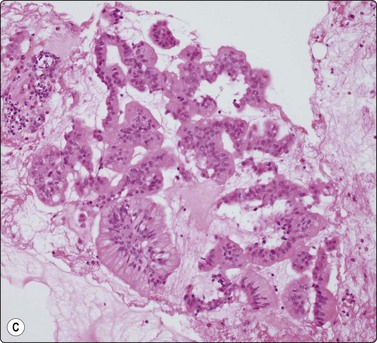

image image image

Fig. 11.12 Intraductal papillary-mucinous neoplasm (IPMN)

(A) Large multilayered papillary structures; note the smooth borders (H&E, IP); (B) Small papillary clusters of cuboidal epithelial cells with mucin vacuoles; the pale mucin in the background is not easily seen (Pap, HP); (C) Cell block showing strips and papillary formations of atypical columnar epithelium (H&E, IP).

image

Fig. 11.13 Intraductal papillary-mucinous neoplasm (IPMN)

Tissue section corresponding to Figure 11.12 (H&E, IP).

Fig. 11.14 Mucinous cystic neoplasm (MCN)

(A, B) Clusters and sheets of relatively monotonous malignant glandular cells showing intracytoplasmic mucin vacuoles (A, MGG, HP; B, H&E, HP); (C) PAS diastase stain on cell block material highlights the intra- and extracellular mucin (PAS/D, IP).

Distinction between IPMN and MCN on cytologic grounds is problematic and requires correlation with clinical, imaging and endoscopic findings as the clinico-radiologic characteristics are very different.

Intraductal papillary-mucinous neoplasms (IPMN) were first described as a distinct entity in the 1980s.83 They are now well characterized as tumors of better prognosis as they have a long intraductal course but eventually will invade into periductal pancreatic parenchyma, and then go on to nodal and distant metastases.84 Both sexes can be affected, but elderly males predominate. IPMN usually involves the main duct in the head of the pancreas but can arise in side branches. As the name implies, the lining epithelium is both papillary and mucinous. The duct system is filled with viscous mucus, leading to a very characteristic endoscopic appearance, where the ampulla of Vater is often seen to be patulous, and draining mucin. The cytology is distinctive (but not entirely specific), showing abundant background mucin, in which sheets and papillary aggregates of cuboidal to columnar, mucin-filled cells are seen (Figs 11.12 and 11.13). Several reports attest to the ability of cytology to diagnose these good-prognosis tumors preoperatively, in conjunction with radiologic and endoscopic features.84-86 In a series of 19 patients, a sensitivity of 82% and specificity of 100% was reported.87

The classic mucinous cystic neoplasm (MCN) is an indolent tumor of middle-aged females, the majority occurring in the tail of the pancreas. These tumors show a spectrum of grade and behavior including benign cystadenomas, borderline forms, and malignant cystadenocarcinomas. The latter obviously has a poorer prognosis if invasion has occurred. Radiologic studies identify a usually discrete and obviously cystic mass in the pancreatic tail. As there is no communication with the pancreatic ductal system, endoscopy does not demonstrate mucinous discharge from a patulous ampulla. As with IPMN, cytology shows a background of copious extracellular mucin, in which cohesive monolayered sheets of mucinous columnar cells are found (Fig. 11.14). These demonstrate regular to irregular honeycombing, with a spectrum of nuclear changes depending on the stage of tumor progression. Epithelial cell cytoplasm is distended with mucin vacuoles.88-91